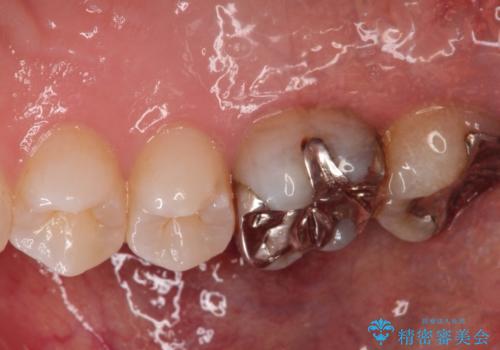

根の神経が細菌に感染するとこのように、膿の出口ができることがあります。

その場合は、根の中の治療(根管治療)が必要になります。